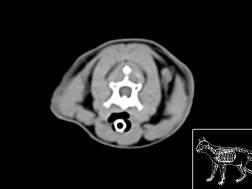

Atlas abdomen du chien SCTO

Scanner tissu osseux

>> 44 coupes

Atlas abdomen du chien SCTM

Scanner tissu mou

>> 43 coupes